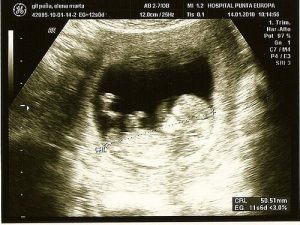

Ultraääni

Ultraäänitutkimus on yleinen toimenpide, jonka avulla paitsi havaitaan mahdollisia sikiön terveysongelmia, myös saadaan ensimmäinen kuva vauvasta sekä selvitetään lapsen sukupuoli, vanhempien näin halutessa.

Ensimmäinen ultraäänitutkimus suoritetaan 10.-12. raskausviikon tienoilla. Tutkimuksessa tarkastetaan sikiön rakenne pääpiirteittäin ja mitataan sikiön niskaturvotus, joka toimii kromosomipoikkeavuuksien ja rakennepoikkeavuuksien riskin osoittajana. Tutkimuksissa on todettu, että alkuraskaudesta havaittu sikiön niskaturvotus on yhteydessä myös synnynnäisten sydänvikojen riskiin.

Jo ensimmäisessä ultraäänitutkimuksessa voidaan havaita suuret ja vaikeat rakennepoikkeavuudet. Jos tutkimus paljastaa korostuneen niskaturvotuksen tai epäilyn rakenteellisesta poikkeamasta, suoritetaan jatkotutkimuksia.

Tutkimus tehdään vatsanpeitteiden päältä tai emättimen kautta ultraäänilaitteen avulla. Laitteen avulla kuvaruudulle muodostetaan kuva korkeita ääniaaltoja, eli ultraääniä, hyväksi käyttäen. Ääniaallot eivät vahingoita sikiötä, mutta tarjoavat meille mahdollisuuden tarkkailla kohdun sisäistä elämää.